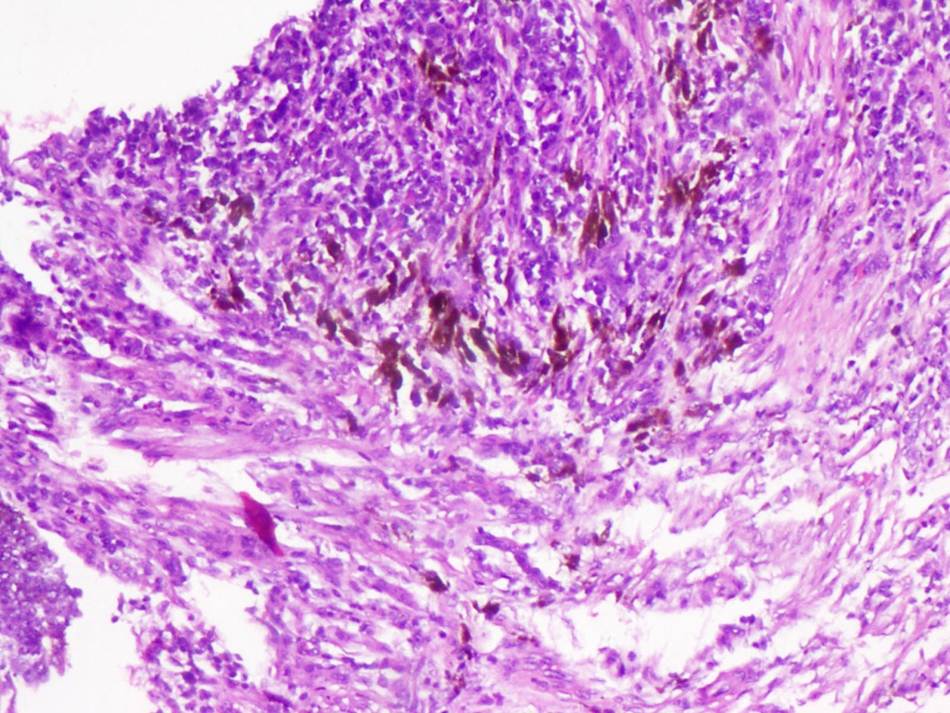

Fig 2: Photomicrograph showing basaloid cells with abundant intracytoplasmic melanin, H&E, 200X